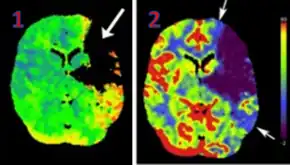

Perfusion CT or CT Perfusion is a type of Perfusion Scanning using Computed Tomography. It is helpful in the evaluation of the vascularity of tissue in the body. In this, the temporal changes in tissue density are measured, providing information about the vascularity of the tissue. In CT perfusion, a contrast media injection is given, and then the scan is taken. The acquired data are post-processed to obtain perfusion maps with different parameters, such as BV (blood volume), BF (blood flow), MTT (mean transit time), and TTP (time to peak).[1][2]

CT Perfusion plays an important role in the assessment of Acute Ischemic Stroke. It is used to create maps of blood flow, blood volume, and mean transit time to assess the tissue and to differentiate between the core and penumbra in stroke.[3]